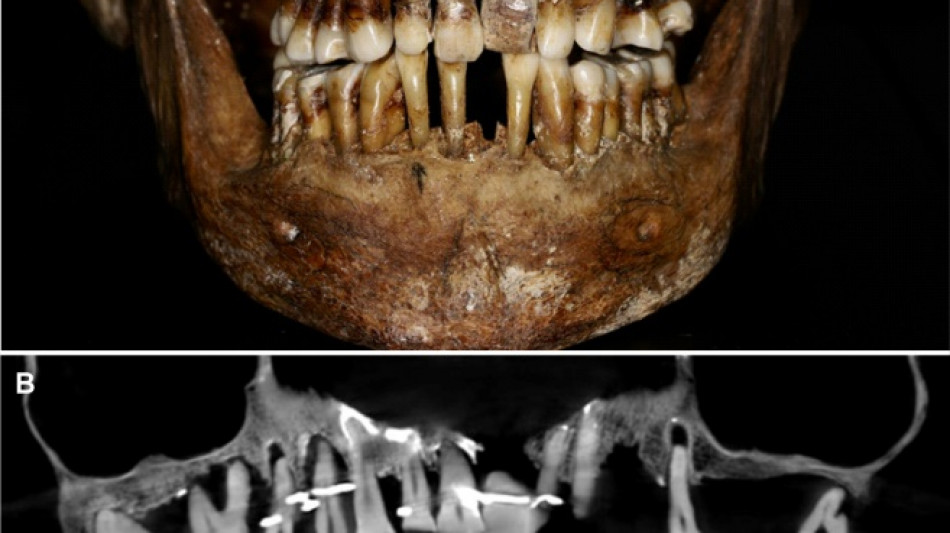

French aristocrat's golden dental secret revealed 400 years on

Scientists have discovered the long-buried secret of a 17th-century French aristocrat 400 years after her death: she was using gold wire to keep her teeth from falling out.

Embalmed in a lead coffin, her skeleton -- and teeth -- were remarkably well preserved.

Thirty-five years later, a team of archaeologists and dentists have identified that d'Alegre suffered from periodontal disease that was loosening her teeth, according to a study published in the Journal of Archaeological Science: Reports this week.

A "Cone Beam" scan, which uses X-rays to build three-dimensional images, showed that gold wire had been used to hold together and tighten several of her teeth.

She also had an artificial tooth made of ivory from an elephant -- not hippopotamus, which was popular at the time.

The gold wires would have needed repeated tightening over the years, further destabilising the neighbouring teeth, the researchers said.